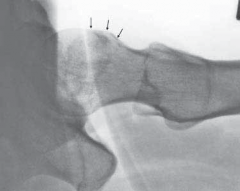

A B FIG 2•A.

Standardized AP pelvic view, showing bilateral acetabular retroversion. On the left hip the anterior (

dotted line

) and the posterior (

full line

) are outlined and form a figure-8 sign.

B.

On the lateral cross-table view, however, an important anterior bump becomes visible.